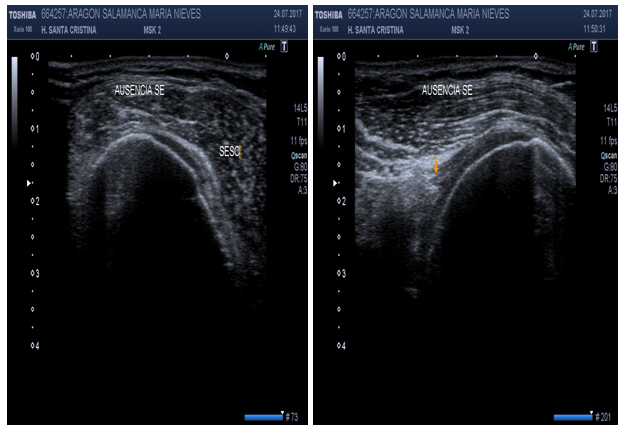

Supraspinatus tendon (short axis) (Figure 8)

Patient position: Patient facing direction of shoulder been studied, 90º to the examiner with hand on back pocket and elbow tucked in (“Marilyn Monroe position”).

Probe position: Probe on sagittal position gives a short axis view. This view is obtained rotating the probe 90º from position.

Scan of structures: Supraspinatus tendon has a convex image like a “tire on a wheel”.

Abnormal findings: A concave image or “flat tire” image may indicate partial tear. A dark line greater than 2mm between supraspinatus and deltoid may denote SASD bursitis.17,18

Figure 7 Sonoanatomy of the supraspinatus tendon (short/transverse axis).

Figure 8 Sonoanatomy of the supraspinatus tendon (long axis).

US can ascertain between normal versus diseased bicipital tendon (partial or full tears, tendinosis). Hyperechoic “fluid ring” around tendon may denote tenosynovitis in short axis, whether a “tear sign” may denote tenosynovitis in long axis (Figure 14). US may identify osteophytes in AC joint and joint effusion (“Geyser Sign”) if inflammation subsides (Figure 15). Small calcific areas in the tendon can be observed specially when assessed dynamically (Figure 16). US is highly sensitive to diagnose SASD bursitis, especially if fluid on scan image is greater than 2mm distance (Figure 17). Dynamic evaluation is capable to determine biceps tendon subluxation or luxation and subacromial impingement (Figure 18).